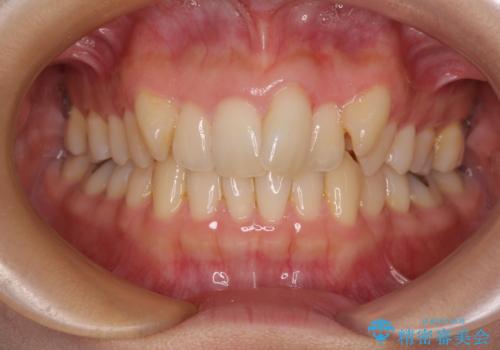

カリエール・ディスタライザーを使用している期間、反対側はワイヤー矯正により叢生を解消していくこととしました。

奥歯の咬み合わせを改善しながら、並行してインビザラインで歯列を整えることとしました。